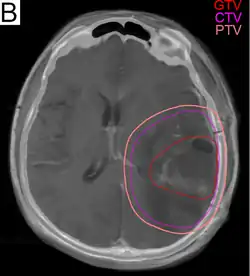

Radiotherapie

.png)

Glioblastome werden, etwa vier Wochen nach einer ggf. stattfindenden Operation, in der Regel mit einer Gesamtdosis von 60 Gray in etwa 30 Sitzungen bestrahlt. Bei höherem Patientenalter und/oder schlechter Prognose können auch Therapiepläne mit geringerer Gesamtdosis zum Einsatz kommen. Besondere Bestrahlungsverfahren, Brachytherapie oder Radiochirurgie bieten keinen Überlebensvorteil gegenüber der Standardtherapie.[16][23]